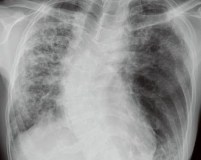

Из-за отложения определенных молекул в лизосомах у 68% пациентов в конечном итоге развиваются симптомы легочного фиброза с рестриктивной дыхательной недостаточностью, тогда как у 45% пациентов аномалии выявляются на рентгенограмме грудной клетки. При синдроме Германского-Пудлака существует повышенный риск развития кардиомиопатии, хронической сердечной недостаточности. У 15% пациентов проявляется клинический гранулематозный колит.

• Инструментальные методы. Учитывая высокую частоту респираторных инфекций и фиброза, пациентам требуется рентгенография органов ГК в 2-х проекциях, КТ легких, спирография. Для исключения органических причин желудочно-кишечного кровотечения применяют ЭФГДС, колоноскопию.